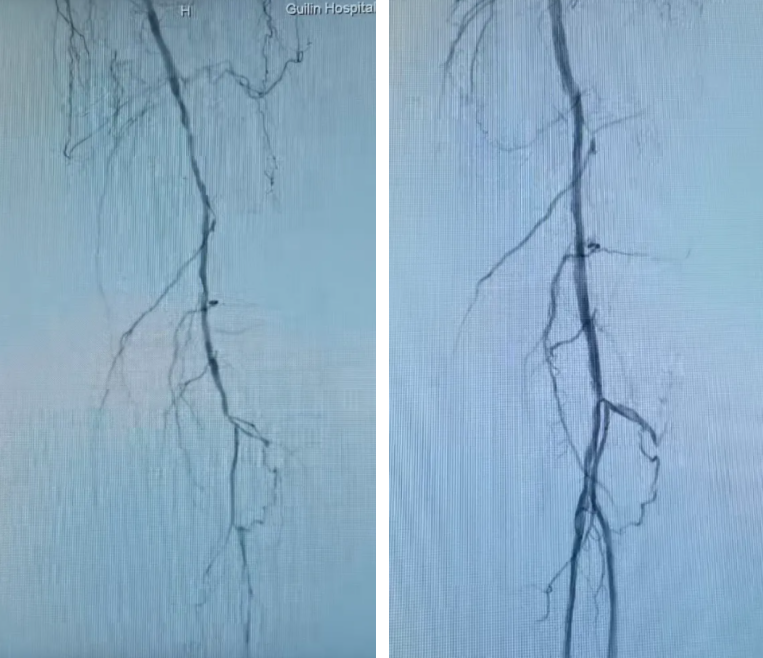

IVUS引导下的准分子激光斑块消蚀术中影像

术前(左)、术后(右)小腿动脉的IVUS对比